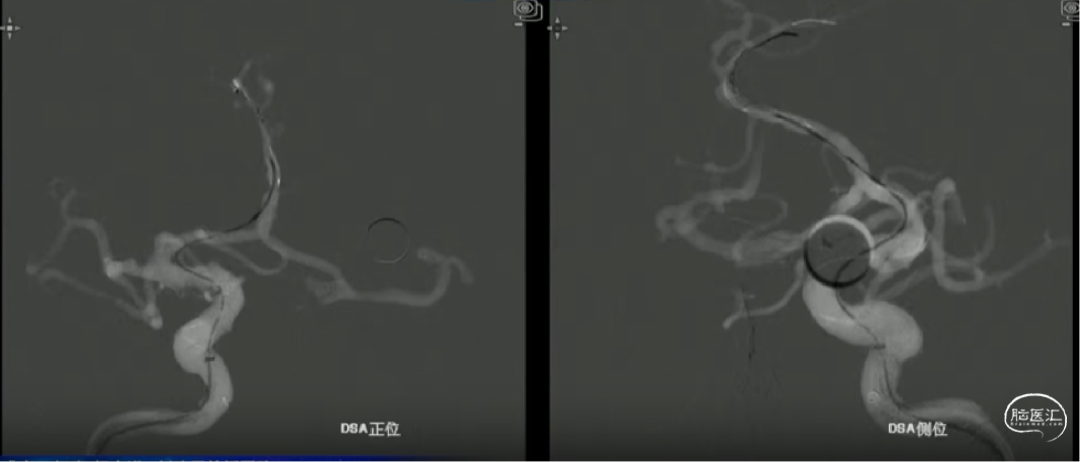

如意中段释放

心玮“如意”血流导向密网支架相较于其他钴铬合金材质,密网支架略软,释放远端动脉瘤不会影响血管的走形。

中段释放后,造影,动脉瘤滞留明显,支架贴壁打开良好,支架位置合适。

如意完全释放

支架整体释放后,贴壁良好,打开良好,无需再次按摩支架贴壁,故上高心玮DMC21微导管,回收带镍钛球囊的输送导丝。

术后即刻造影,动脉瘤滞留明显,载瘤动脉管腔通畅无狭窄,支架贴壁理想。

“如意”血流导向密网支架很好打开,镍钛小球助力支架更好的二次打开,支架释放中就能达到自膨打开,无需按摩,是一款各方面性能都不错的支架。